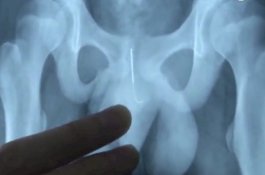

Bocah 13 Tahun Masukkan Jarum ke Itunya Agar Tidak Ketiduran Kerjakan PR